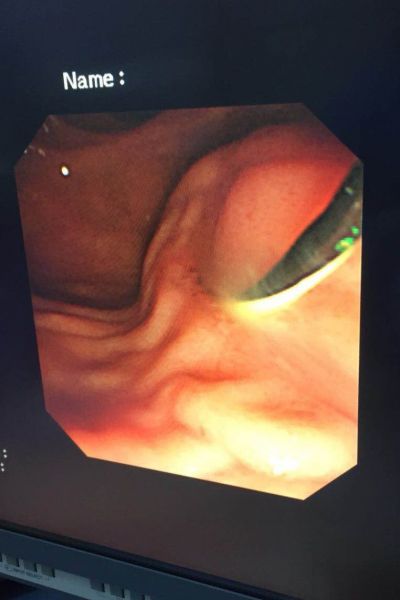

患者是一位80 岁的老年女性,因“腹痛、发热、黄疸2天”来我院求治,入院时体温39℃,血压80/40mmHg,胆红素282mmol/L,腹部CT提示胆总管下段结石,诊断胆总管结石并急性化脓性胆管炎明确。按照传统治疗方案,患者需要行外科手术。但此时手术风险极高,且术后患者需较长时间保留T管引流。有鉴于此,科主任李学锋、李凯组织消化科田家晖副主任医师、向仍运主治医师以及肝胆外科专家进行会诊,最终决定,予以患者施行急诊鼻胆管引流术。经过有序的术前准备,在外科的通力配合下,在李学锋主任和李凯主任的指导下,向仍运主治医师通过十二指肠镜对胆总管进行插管,插管成功后首先抽吸出脓液减压,再对胆总管进行造影显示出结石的位置、形态及大小,最后在结石以上胆管置入鼻胆管引流。手术过程非常顺利,历时不到40分钟,术后患者疼痛即消失,血压、白细胞、胆红素很快恢复至正常。

ERCP即逆行胰胆管造影,用十二指肠镜在X线透视下对胆管、胰管进行显影,并对病变进行相应治疗,属于四级手术。特别适用于胆总管结石、急性化脓性胆管炎、梗阻性黄疸患者。该操作无需麻醉,痛苦小(相当于做胃镜)。